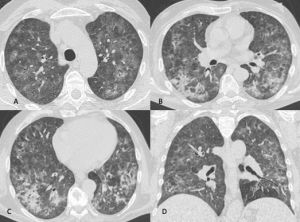

In TCAR si caratterizza per la presenza di aree a “vetro smerigliato” diffuse in entrambi i polmoni come la maggior parte delle polmoniti virali descritte di seguito, queste aree tuttavia si contraddistinguono per la prevalente distribuzione subpleurica e per la presenza nel contesto di ispessimento liscio dei setti interlobulari (Figura 1). Versamento pleurico e linfadenopatie sono reperti più rari.

Figura 1: Uomo di 75 anni con infezione da SARS-CoV-2. Le immagini TC assiali (A-B-C-D) e ricostruzioni MPR sul piano sagittale (E) e coronale (F) mostrano la tipica presentazione della polmonite da COVID-19 caratterizzata dalla presenza di aree di aumentata densità con aspetto a “vetro smerigliato” cui si associa ispessimento liscio dei setti interlobulari che mostrano prevalente distribuzione subpleurica. La localizzazione delle aree di iperdensità in sede subpleurica è caratteristica di questa infezione come evidenziato particolarmente nell’immagine A in cui le aree a “vetro smerigliato” si dispongono lungo la scissura del lobo accessorio dell’azygos e nell’immagine E in cui è evidente la distribuzione delle alterazioni lungo le scissure.